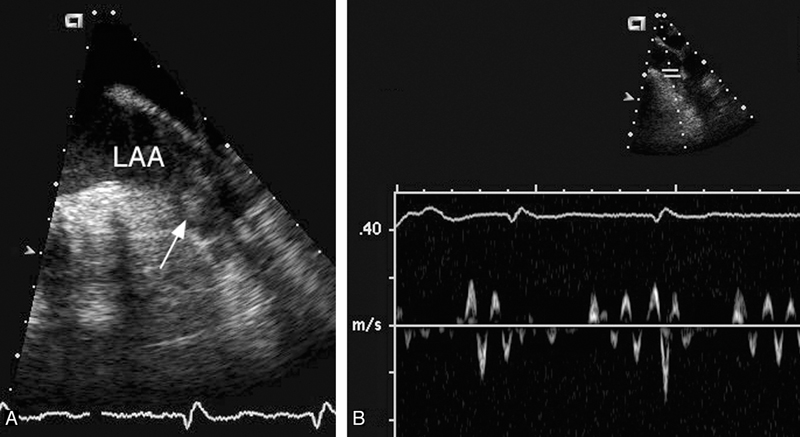

فحوصات تشخيصية لبعض امراض القلب والشرايين التاجية